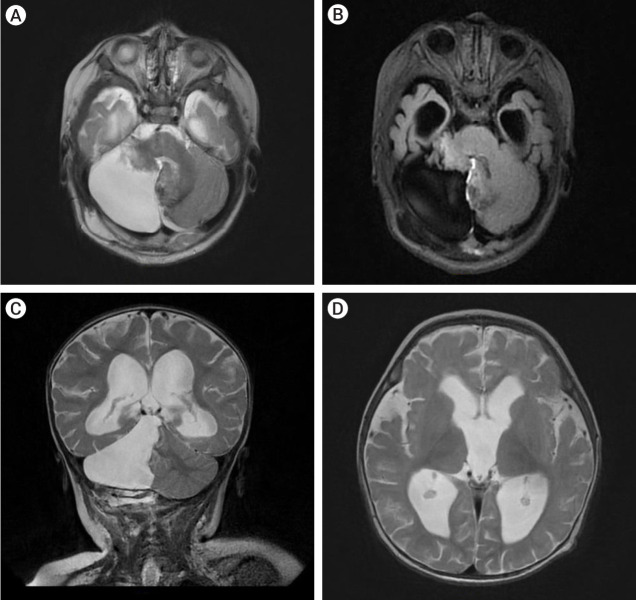

儿童巨大小脑海绵状瘤非常罕见,必须与出血性小脑肿瘤区分开来。巨型小脑海绵状瘤的诊断和治疗具有挑战性,但完全的手术切除可带来良好的结果,大多数病例的神经功能可完全恢复。我们报告了一例八个月大的婴儿,他被诊断出患有巨大海绵状瘤,导致继发性梗阻性脑积水,并伴有神经精神症状。患者接受了枕骨下入路的副颅骨开颅手术,完全切除了海绵瘤。经过九个月的观察,患儿的行走能力有所改善,神经系统也完全康复。我们还进行了文献综述,确定了包括本病例在内的 11 例儿童巨大小脑海绵状瘤病例。我们对这些数据进行了分析,以确定儿童巨大小脑海绵状瘤的临床特征、治疗方法和结果。

Giant cerebellar cavernomas in children are rare and must be differentiated from hemorrhagic cerebellar tumors. The diagnosis and treatment of giant cerebellar cavernomas is challenging, but complete surgical resection can lead to favorable outcomes and complete neurological recovery in most cases. We present a case of eight months old baby who was diagnosed with a giant cavernoma resulting in secondary obstructive hydrocephalus with neuropsychiatric presentations. The patient underwent a paramedian craniotomy surgery with a suboccipital approach and complete surgical resection of the cavernoma was done. Over nine months of observation, the child showed improvement in their ability to walk and fully recovered from a neurological perspective. We also conducted a literature review to identify eleven cases of giant cerebellar cavernomas in children, including our case. The data were analyzed to determine the clinical features, treatment, and outcomes of giant cerebellar cavernomas in children.